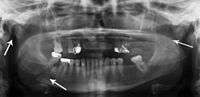

Panoramic radiography

Panoramic radiographs are tomograms where the mandible is in the focal trough and show a flat image of the mandible. Because the curve of the mandible appears in a 2-dimensional image, fractures are easier to spot leading to an accuracy similar to CT except in the condyle region. In addition, broken, missing or malaligned teeth can often be appreciated on a panoramic image which is frequently lost in plain films. Medial/lateral displacement of the fracture segments and especially the condyle are difficult to gauge so the view is sometimes augmented with plain film radiography or computed tomography for more complex mandible fractures.

Panoramic radiograph of a simple mandible fracture of the right mandibular body, minimally displaced. Note that the teeth to the left of the fracture do not touch- lateral oblique image demonstrating a fractured mandible.